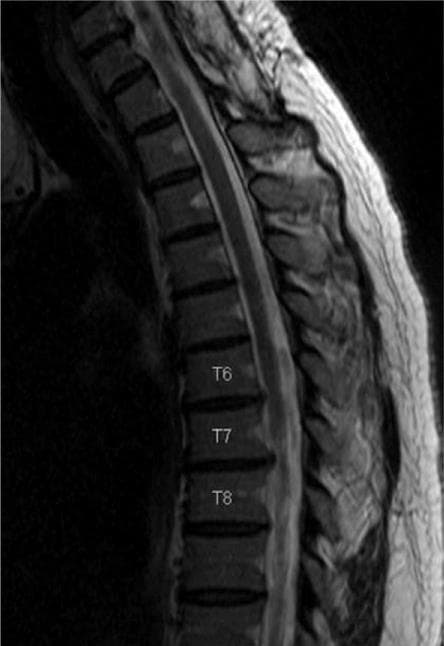

Протрузії та грижі грудного відділу міжхребцевих дисків зустрічаються рідше, ніж у шийному або поперековому відділах хребта. Однак, насправді, це трапляється не рідко.

Нами розроблена методика, що дозволяє успішно проходити голкою в потрібний міжхребцевий диск і проводити в центр його лазерний промінь. Дія лазерного променя така ж, як і при лікуванні шийних або поперекових дисків.

Також розроблена методика, що дозволяє безпомилково виявляти той диск, який є причиною болю.